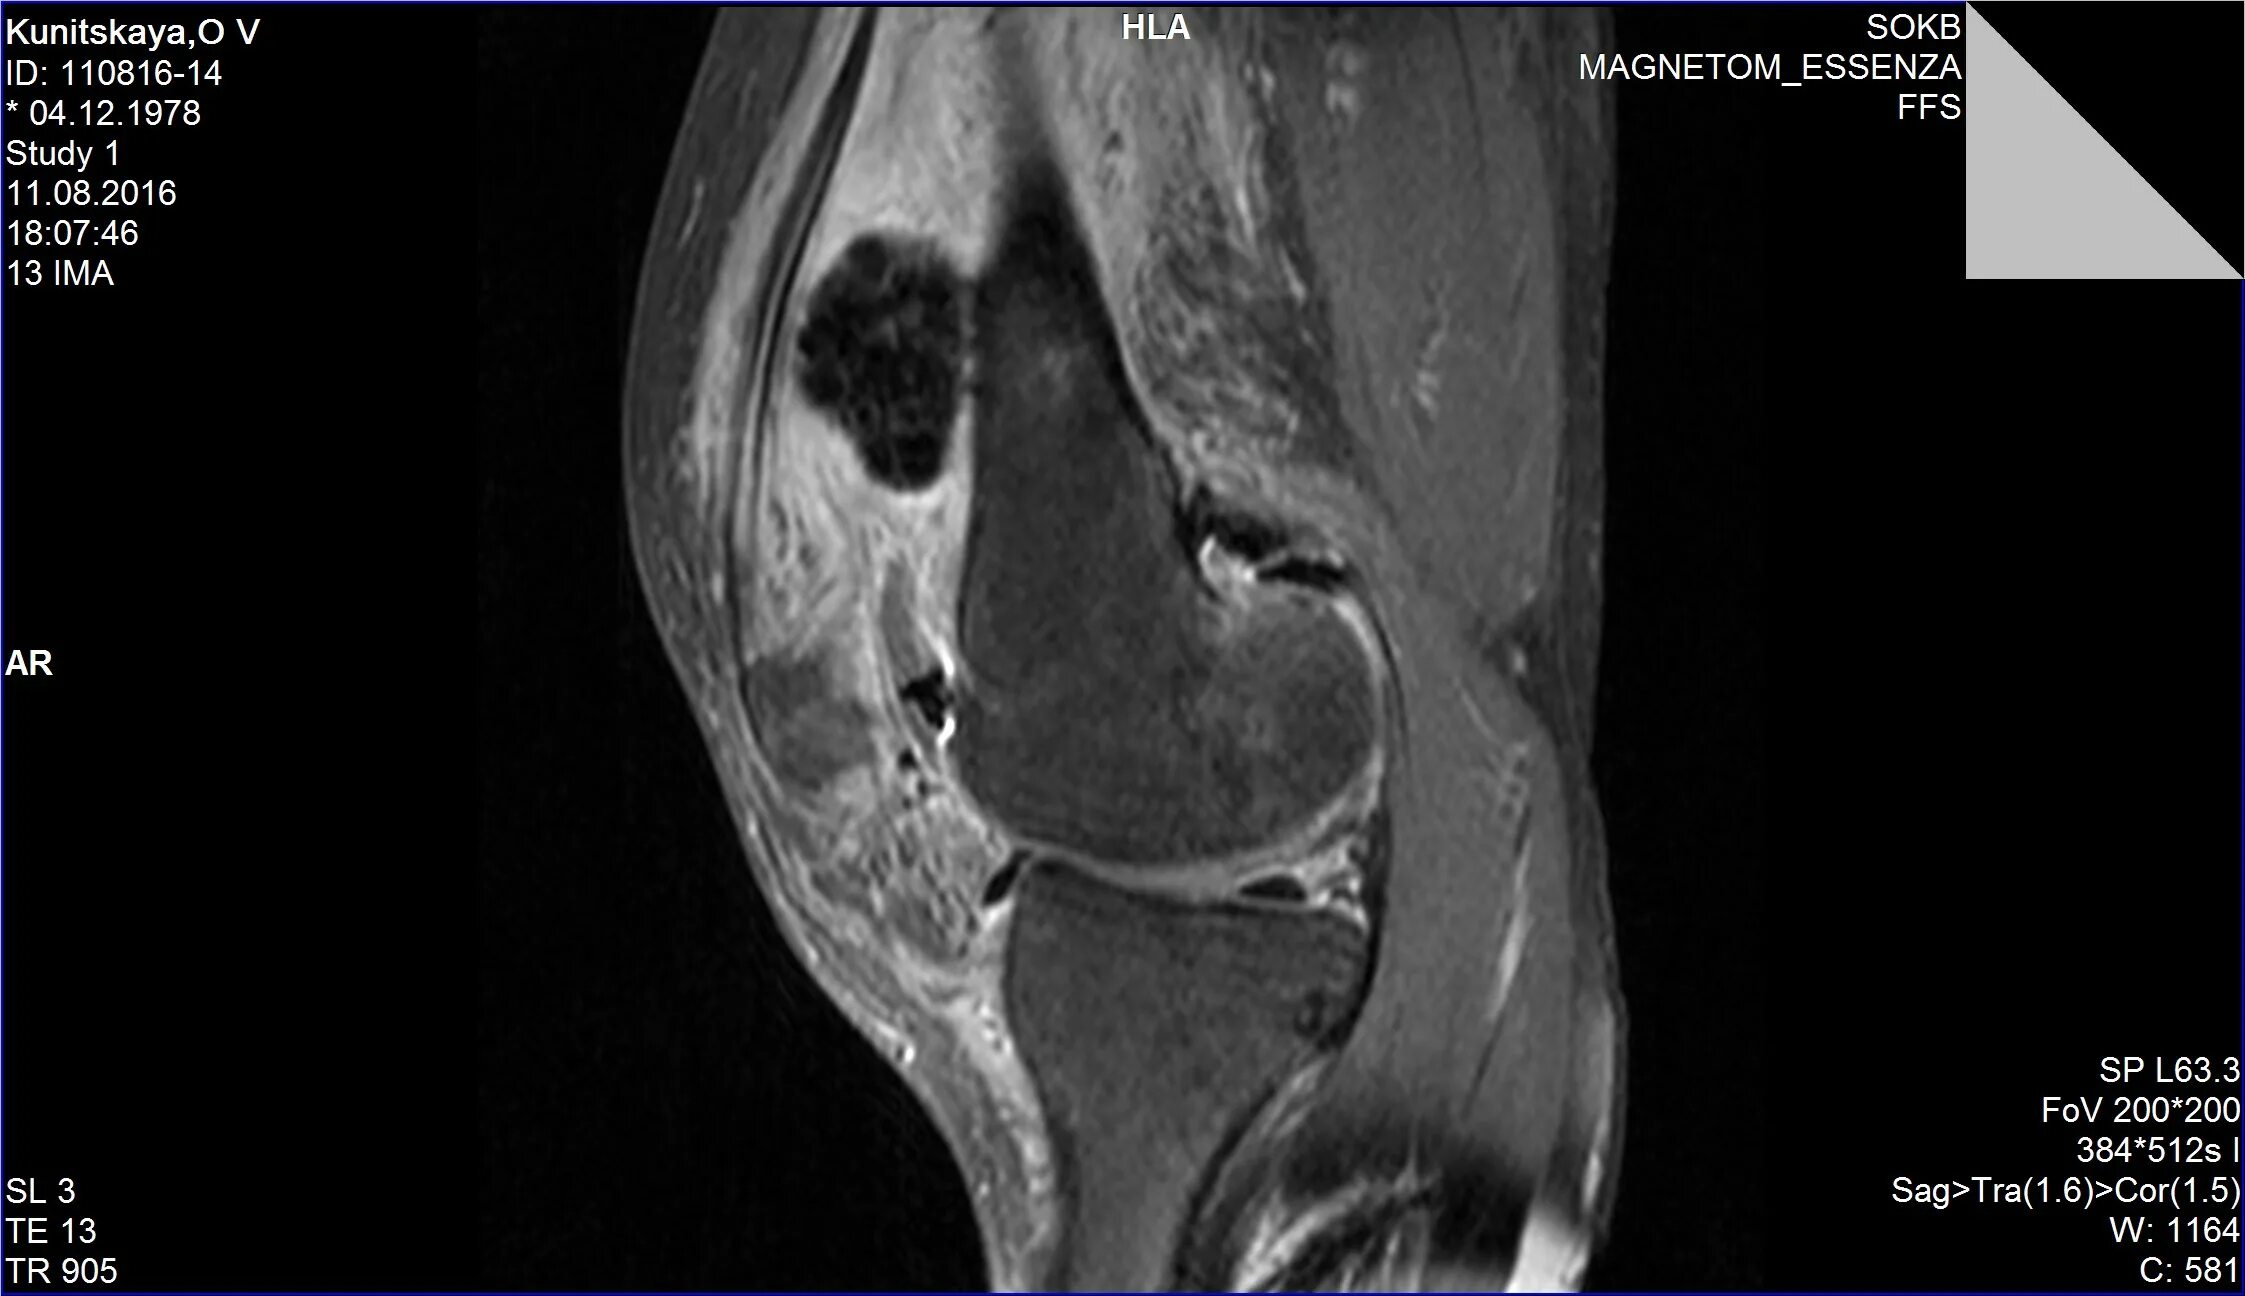

Пигментный виллонодулярный синовит